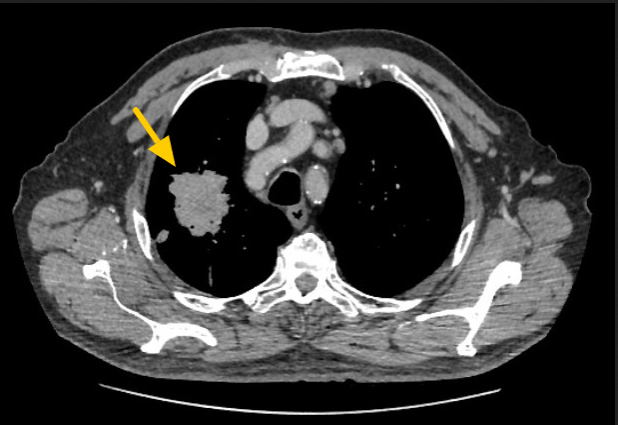

Por estar disponible la TC de pelvis previamente realizada, se procedió a fusionar las imágenes (figs. 5 y 6) en las cuales se verifica conexión de la vejiga con una hernia inguinal (que no fue reportada en la TC) y la conocida lesión lítica en ala ilíaca derecha, con componente de partes blandas que se extiende al músculo ilíaco engrosado, sin reacción perióstica, característica de secundarismo. En una nueva TC en busca de la neoplasia primaria, se identifica una tumoración sólida en lóbulo superior del pulmón derecho, de aproximadamente 57 x 44 mm (fig. 7), sugestiva de carcinoma broncopulmonar (CBP).